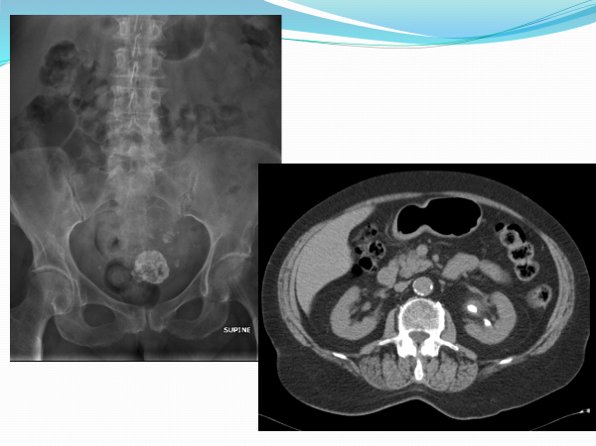

Calcified fibroid; PUJ & left renal stone not visible on KUB

This is a calcified fibroid.